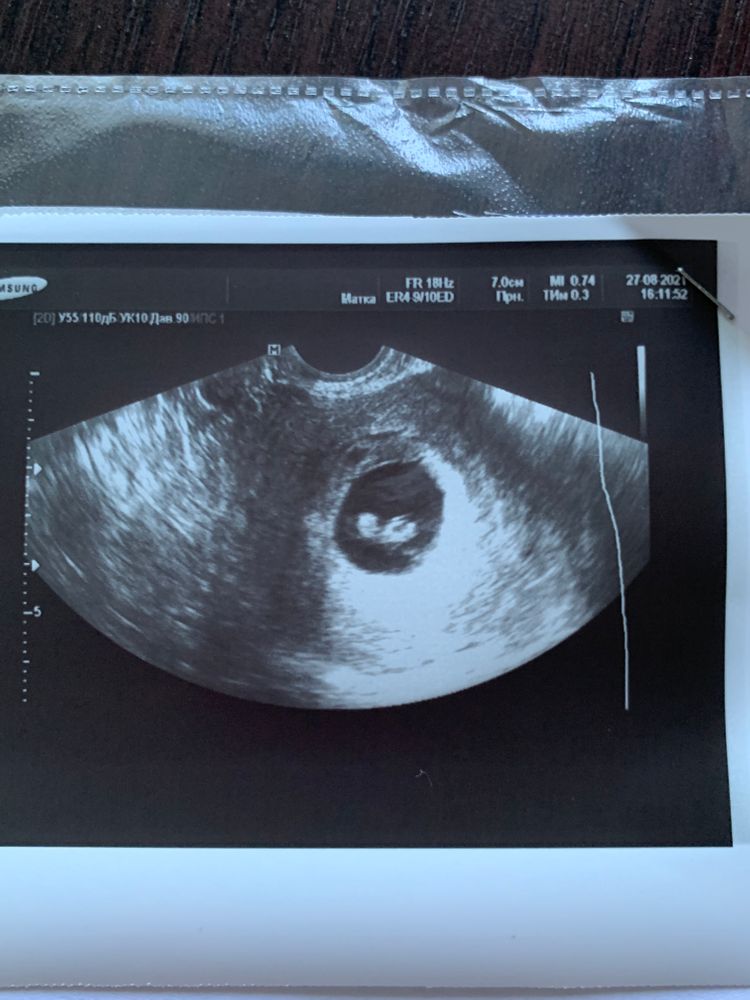

7,3 недели УЗИ

Lenni, нет ктр 7,5 мм это на срок 6+4 Изображение

Акушерский написала по размеру эмбриона,но то что отстаёт на 5 дней это норма,к скринингу догонит

Указала она акушерский. Она Вам и сверху почему-то написала срок по последним М и тоже указала 6,5. Видимо ошиблась с подсчетами. У Вас в нормы все вписывается, не парьтесь, на таком сроке разброс по размерам может быть приличный.